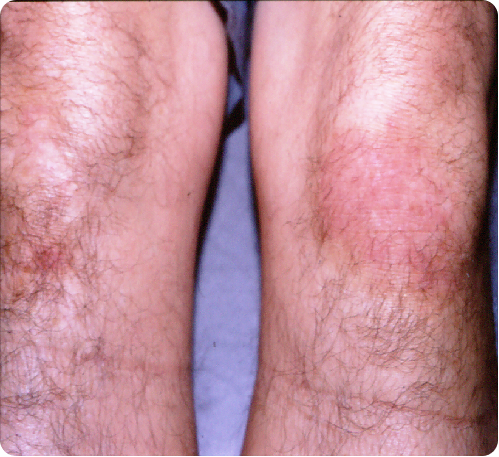

Psoriasis is a chronic skin condition that affects up to 7.5 million people in the United States alone. It is characterized by red, scaly patches of skin that can be itchy and uncomfortable. While there is no cure for psoriasis, there are a range of treatments available that can help manage the symptoms and reduce flare-ups. One of these treatments is light therapy, also known as phototherapy, which has been used to treat psoriasis for over 50 years. In today’s chapter, GSD will discuss different light therapies for psoriasis and what’s the best method to help treat the disease.

Excimer UV-Light is an effective treatment for psoriasis. It can reduce the severity of symptoms and improve the overall appearance of the skin. Studies have shown that this therapy is particularly effective for treating plaque psoriasis, which is the most common type of psoriasis. Other benefits of light therapy for psoriasis include:

Improved appearance of the skin: This therapy can help to improve the appearance of the skin by reducing redness and scaling. This can help to boost self-esteem and confidence in people with psoriasis.